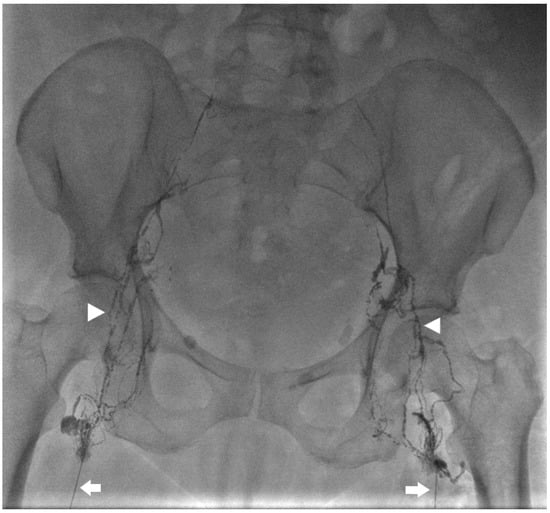

Kaminski et al. compared lymphangiography only versus lymphangiography and embolization. The median amount of iodized oil (lipidol) used was 12 mL (range 8–20 mL) with 20 mL used in all cases of lymphangiography only. Embolization of the target lymph vessel was performed with coils and/or liquid embolics (Histoacryl) diluted with ratio 1:1–1:5. Coils were used in the embolization of large lymph vessels to prevent distal migration of glue to the venous system (Figure 3 and Figure 4). Glue-only embolization was performed in peripheral lymphatics with no risk of glue migration or lymph node embolization. When embolization was not feasible, interstitial lymph node embolization was performed. Dietary restriction with Medium Chain Triglyceride supplement was prescribed for 2–3 days post-procedure. Embolization achieved 26/28 (92.9%) and 11/12 (91.7%) clinical success in traumatic and non-traumatic thoracic chylous effusion, respectively; lymphangiography only achieved 1/2 (50.0%) and 1/6 (16.7%) in traumatic and non-traumatic thoracic chylous effusion, respectively. Clinical success in combined abdominothoracic chylous effusion was achieved in 2/3 (66.7%) and 0/5 (0.0%) of embolization and lymphangiography only patients, respectively. Overall success of thoracic intervention was 39/48 (81.3%) with a significant difference between traumatic and non-traumatic groups. Complications were seen after lymphatic embolization in 5 patients with one grade 1, two grade 2, one grade 3, and one grade 4 as follows: pulmonary glue migration, upper extremity vein thrombosis, edematous pancreatitis, bleeding from branch of left hepatic artery, biliary peritonitis [22].

Figure 3. Spot image from an intra-nodal lymphangiogram for a 59-year-old patient with traumatic chylothorax after esophagectomy. Bilateral 25 G needles (arrows) are used to inject lipiodol into the inguinal lymph nodes and up the lymphatic vessels (arrow heads).

Figure 4. Spot image from the same patient in Figure 3 showing lipiodol within the thoracic duct (arrow) and coils at the distal thoracic duct (arrowhead) to address a leak in the mediastinum (star).